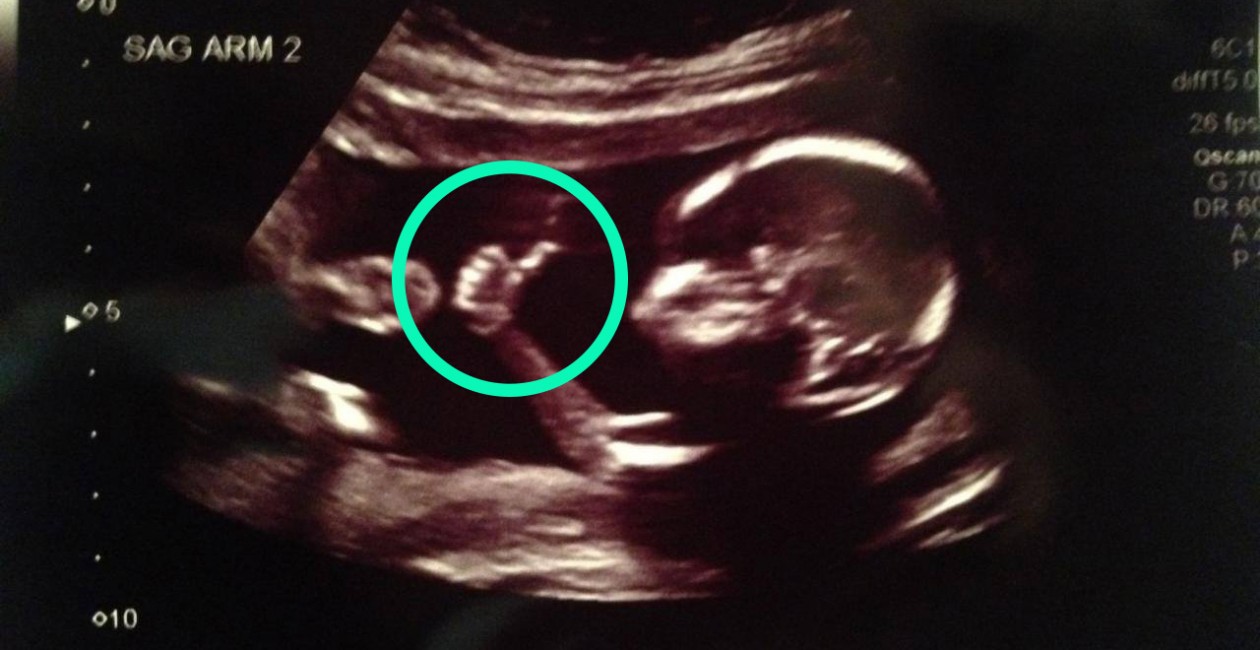

7. They anticipate touch. Researchers at the University of Durham used 4D ultrasound scans to track the movements of fetuses unborn babies during the third trimester and found that, by the nine-month mark, fetuses unborn babies started opening their mouths in relation to directed movements. This suggests they'd finally put two and two together -- i.e., "Hey, hand headed toward mouth for some quality thumb sucking! Open up!"